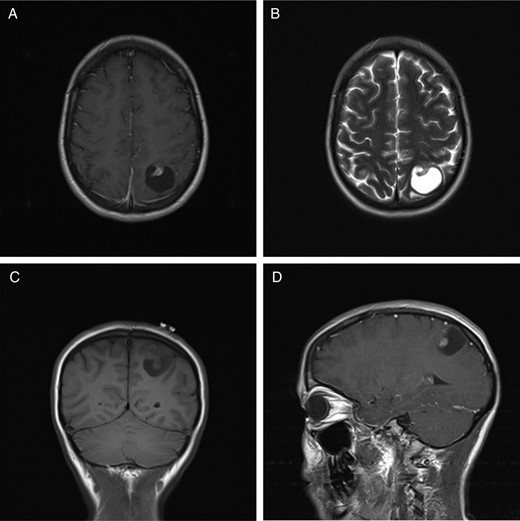

A 27-year-old lady presented to the hospital with a single focal seizure. She described flashing lights in her right visual field. Neurological examination was normal and she had no visual field defects or sensory disturbances. Magnetic resonance imaging (MRI) revealed a 2.8 × 2.9 cm lesion in the left parietal lobe, which was predominantly cystic with a murally enhancing nodule (Fig. 1). There was no enhancement of the cyst wall itself. The cyst content was isointense to cerebrospinal fluid (CSF) on T1- and T2-weighted imaging. There was minimal perilesional inflammatory change or mass effect and no restricted diffusion.

MRI of a supratentorial ependymoma that presents as a single cyst with a contrast-enhancing mural nodule. (A) T1-weighted axial image with contrast. (B) T2-weighted axial image. (C) T1-weighted coronal image without contrast. (D) T1-weighted image in a sagittal plane with contrast.